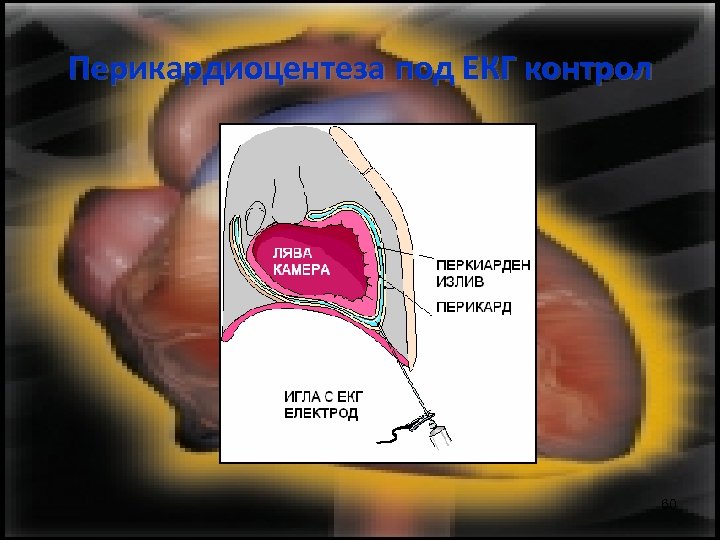

Перикардиоцентеза под ЕКГ контрол 60